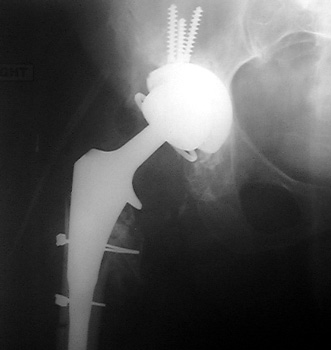

Dislocated femoral component secondary to steep acetabular cup

inclination, pre and post revision. Note constraining ring about femoral head,

which helps maintain head in cup